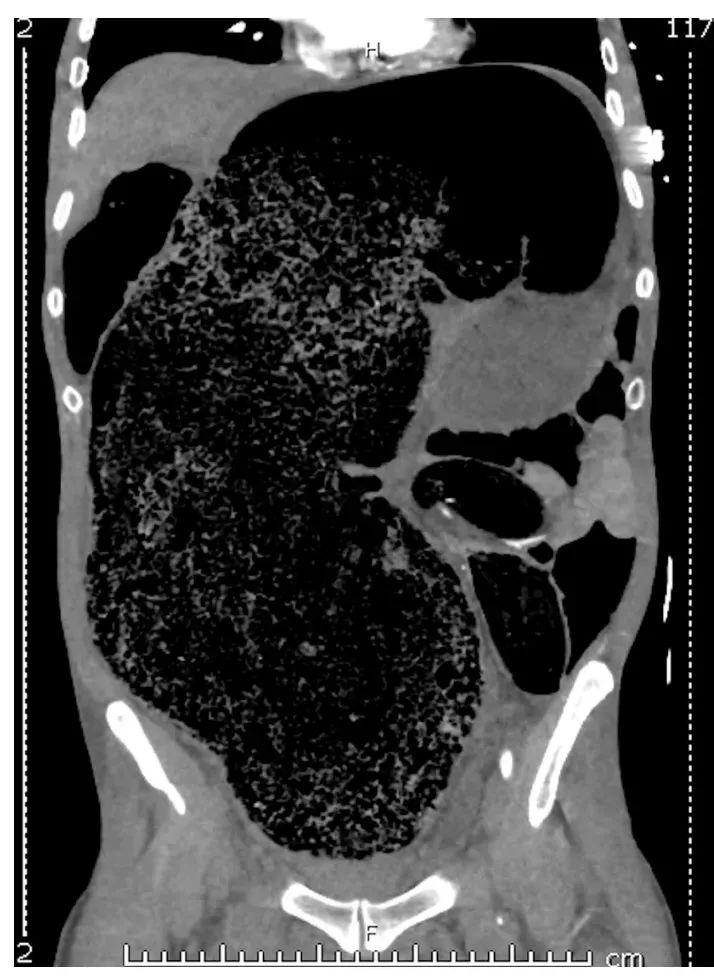

《BMJ 病例報告》曾報道一例 57 歲男性患者因糞便嵌塞引發腹腔間隔室綜合徵和雙下肢急性缺血,最終不得不截肢。[5]這類極端案例雖極爲罕見,但也說明:身體真的可能“被憋壞”。

患者因糞便嵌塞導致的腹部膨脹、血流壓迫與急性下肢缺血情況。來源:參考資料[5]